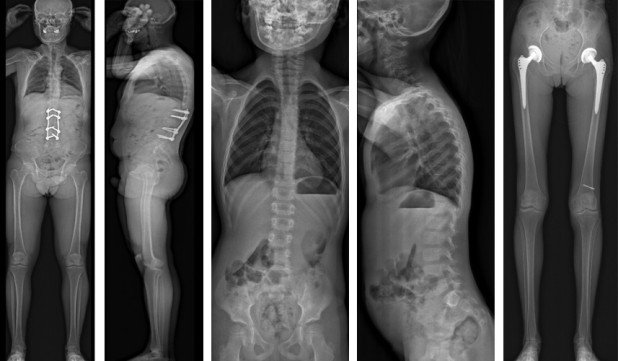

Ganzbein- und Ganzwirbelsäulenaufnahmen

Die Radiologie der Schulthess Klinik gehört zu den Standorten in der Schweiz, die eine der modernsten digitalen Röntgenanlagen für Ganzbein und- Ganzwirbelsäulen Aufnahmen mit einer 2D und 3D Technik anbieten können.

An dieser modernen Röntgenanlage können in kürzester Zeit Ganzbein- und Ganzwirbelsäulenaufnahmen in 2D Technik gemacht werden. Hierzu werden im Gerät zwei Röntgenröhren je nach Aufnahmetechnik aktiviert. Während der Aufnahme zur Erstellung des Röntgenbildes fahren Röntgenröhre und Detektor parallel miteinander. Die Messdaten werden gespeichert und über einen Prozessor eines Computers anschliessend zu einem sichtbaren Röntgenbild berechnet.

Die Röntgenaufnahmen ermöglichen dem behandelnden Arzt die Berechnung einer Achsenbestimmung. Zudem ist es anhand der bereits vorhandenen Patientendaten mit Unterstützung einer speziellen Software möglich, eine 3D-Rekonstruktion zu berechnen, in der eine Bildsimulation an der Wirbelsäule und der Beinachse dargestellt wird.